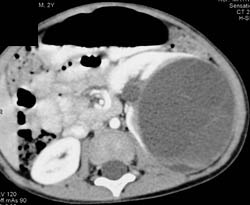

Cystic Renal Cell Carcinoma